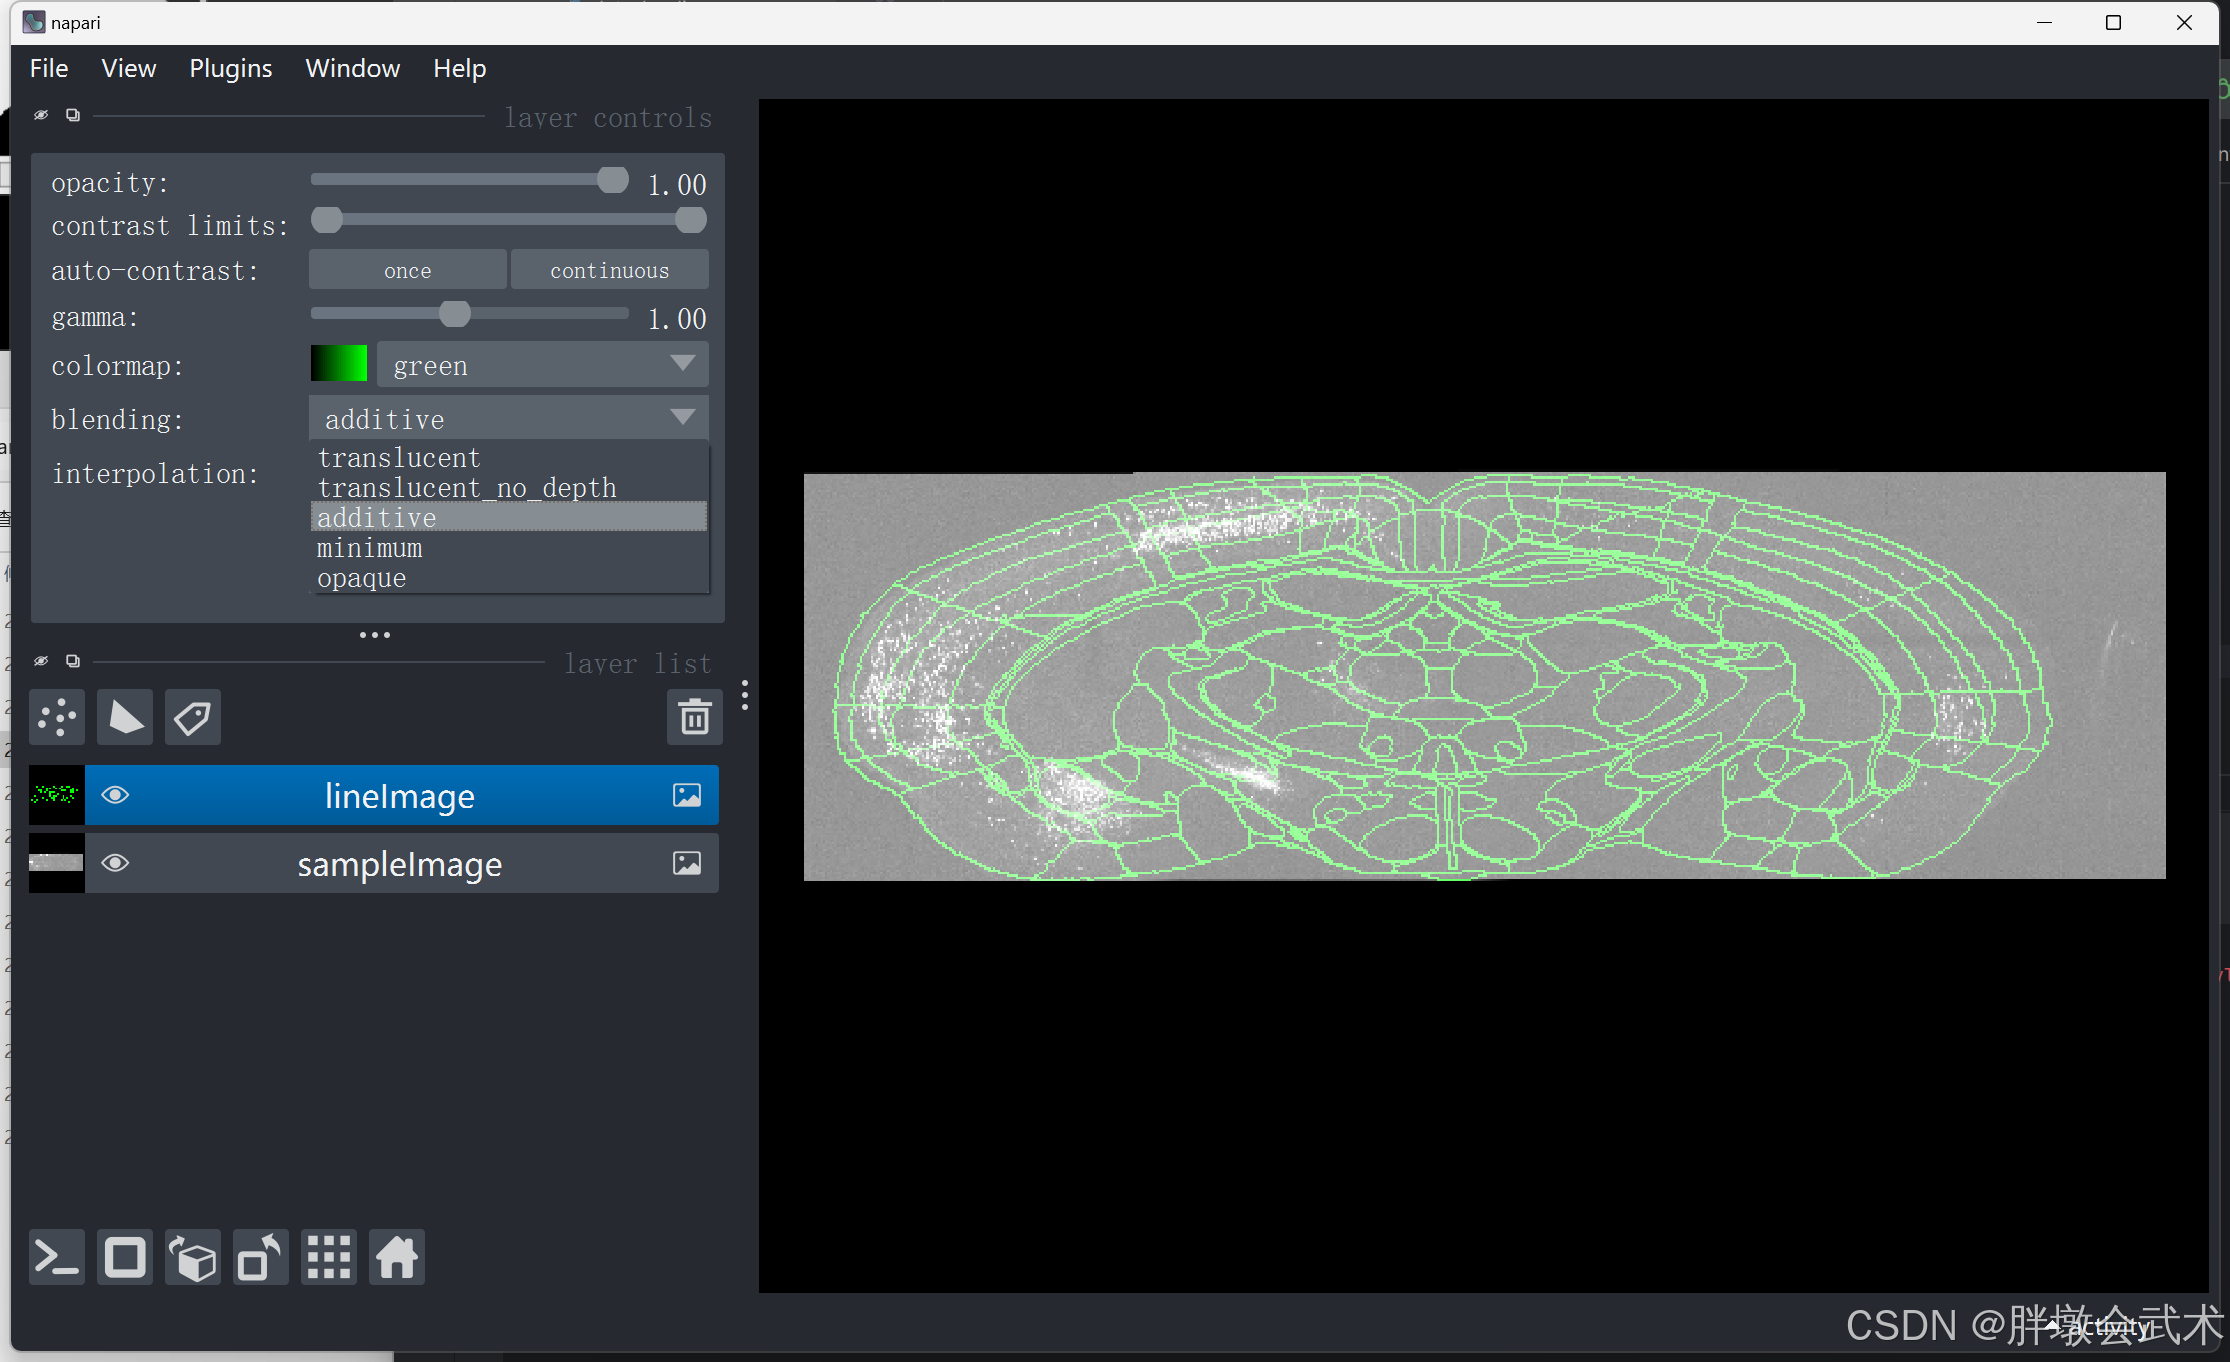

3.2.1、(手动)多通道叠加显示(rendering=“additive”)

import napari

import tifffile

if __name__ == '__main__':

image_path1 = r'F:\py\sampleImage.tif'

image_path2 = r'F:\py\lineImage.tif'

sampleImage = tifffile.imread(image_path1)

lineImage = tifffile.imread(image_path2)

viewer = napari.Viewer() # 创建 napari 视图

viewer.add_image(sampleImage, name='sampleImage')

viewer.add_image(lineImage, name='lineImage', colormap='green', rendering="additive")

napari.run() # 显示 napari 视图

# 启动 napari 后设置参数